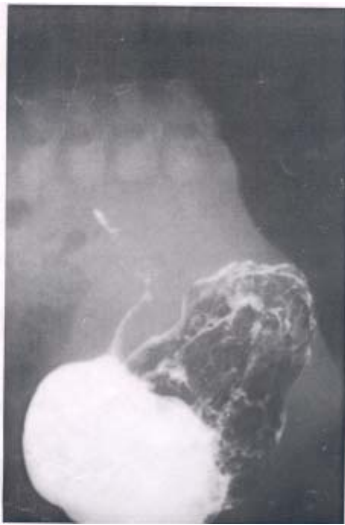

76 1 歲男嬰上消化道鋇劑檢查如下圖,下列敘述何者錯誤?

(A)術前須做內視鏡檢查和組織切片以獲得確實診斷 (B)上圖呈現胃出口(gastric outlet)可能有阻塞 (C)為先天性胃幽門肥大狹窄(congenital hypertrophic pyloric stenosis) (D)超音波掃描有助於對該病灶的診斷